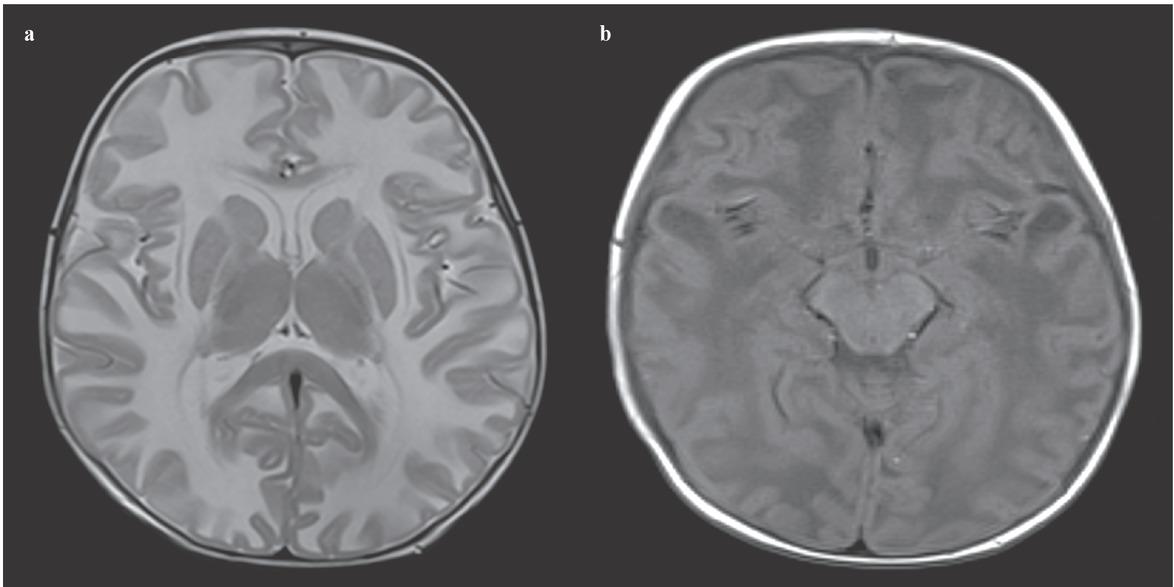

(a) Axial T2 weighted MRI shows bilateral, diffuse, symmetric hyperintense lesions in the cerebral white matter. (b) Axial T1 weighted MRI shows bilateral temporal cysts.